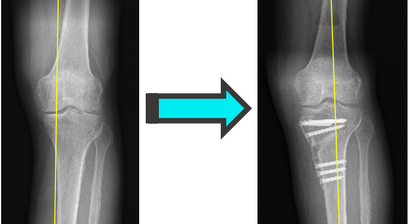

Bei Ihrem Besuch werden Sie von mir ausführlich über sämtliche moderne Therapie-und Operationsverfahren bei Sportverletzungen (z.B. Kreuzbandriss, Meniskusriss, Bandverletzungen, Patellaluxation), Abnutzungen (Knorpelschaden, Arthrose) und Fehlstellungen beraten.

Mein fachärztlicher Schwerpunkt liegt in der Behandlung des Kniegelenks. Durch die internationale Ausbildung an einer Knieklinik, aktive Mitgliedschaft in zahlreichen wissenschaftlichen Fachgesellschaften sowie langjährige Erfahrung führe ich auch komplexe Knieoperationen (u.a. Meniskustransplantation) und Kombinationseingriffe in höchster Fallzahl in Wien durch.